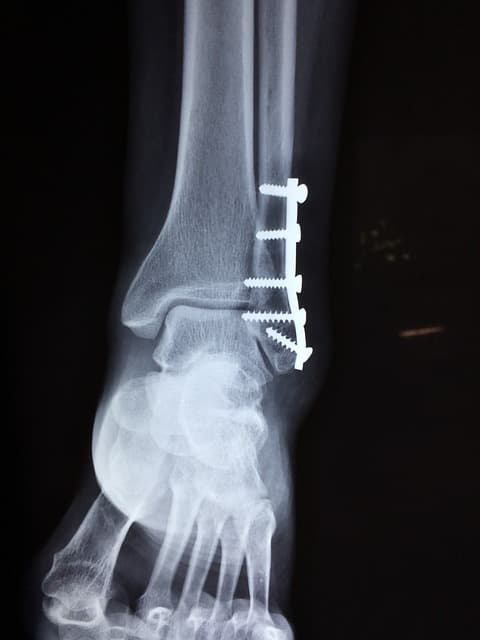

2. X선은 파장이 매우 짧아서 물체에 대한 강한 투과력을 가지고 있습니다. 특히 단파장인 X선일수록 강한 투과력을 가집니다. 물체에 대해서 투과력이 강한 X선을 Hard X-ray, 비교적 투과력이 약한 X선을 Soft X-ray이라 합니다. X선을 투과하는 정도는 물체의 종류에 따라 다르며, 원자번호와 밀도가 높은 물질일수록 X선이 투과하기 어렵습니다.

X선은 물체에서 투과뿐만 아니라 흡수와 산란이 일어나므로 물체를 통과한 후에는 감쇠가 일어납니다. 물체의 두께, 원자번호, 밀도 등이 다르면 감쇠 효과가 다르므로 물체의 종류에 따라 투과한 X선의 강도가 다릅니다. 따라서 물체의 뒤쪽에 형광판 또는 사진필름을 놓으면 물체 내부의 원자번호와 밀도의 변화 등에 대응하는 명암 또는 농도 차이에 의해서 물체의 내부상태를 알 수 있습니다. 이런 X선의 감쇠 효과를 이용해 영상을 구성합니다. 의학에서는 이 특성을 이용해 신체 내부를 검사합니다. 또한 X선을 이용한 비파괴검사도 이 특성을 이용한 것입니다.